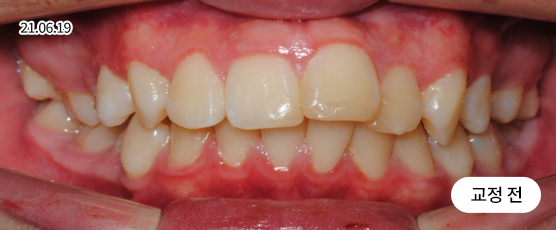

덧니교정 Solution

덧니는 악궁 크기, 얼굴형, 골격 등을 고려해 발치, 비발치를 현명하게 판단하여 치료합니다.

치아가 정렬될 공간을 확보하기 위해, 경우에 따라 소구치(작은 어금니)를 발치할 수 있습니다.